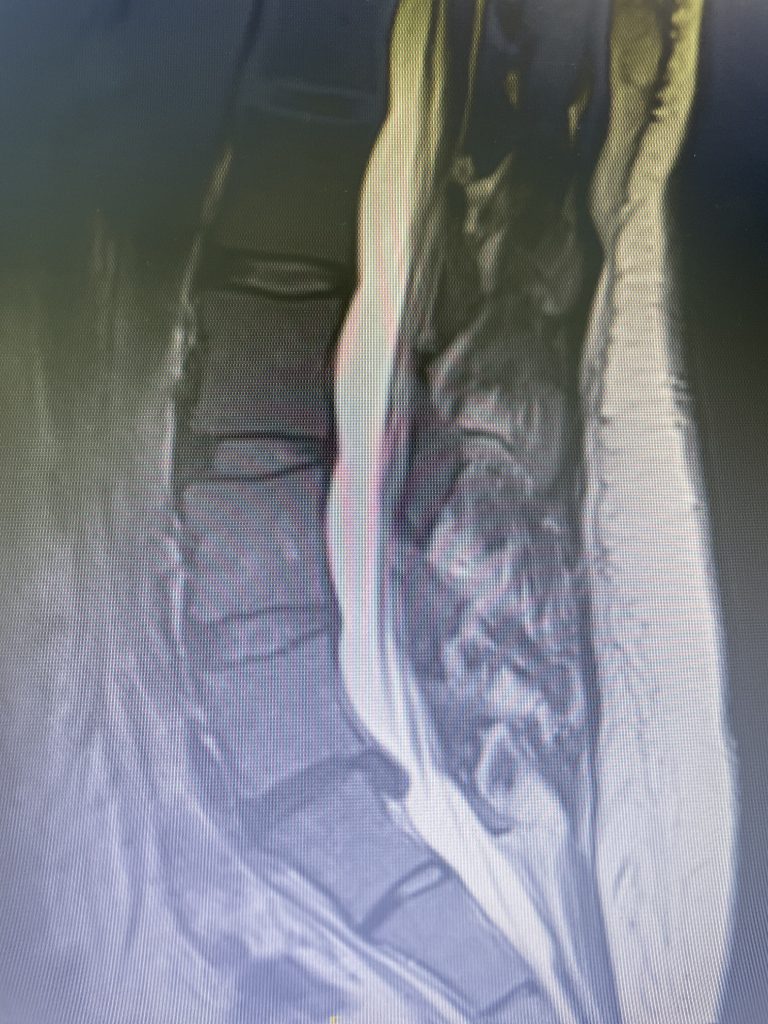

A 35-year-old female presents with severe low back pain and progressive left leg pain. She had initially presented nine months prior with mainly low back pain with mild left leg symptoms. She had an MRI (Fig 1) demonstrating a transitional L5 lumbar vertebra. This L5 vertebra is sacralized in that it is more anatomically associated with the sacral level with a rudimentary disc between it and the segment below. Because of the rudimentary disc there is very little movement at that level, hence more stress is put on the segment above.

As a result, the patient has developed severe degenerative disc disease with collapse and a retrolisthesis above. There is also a left sided disc osteophyte complex that is causing foraminal stenosis and mild thecal sac compression. Up to this point, the patient had failed all means of conservative management including physical therapy, epidural injections, and medicine. Because of the current worsening of left leg pain another MRI was performed which demonstrated a significant increase in the disc herniation with severe thecal sac compression and nerve root compression (Fig 2). It was decided to schedule the patient for decompression, discectomy, and fusion because of the progression of disc herniation and retrolisthesis.